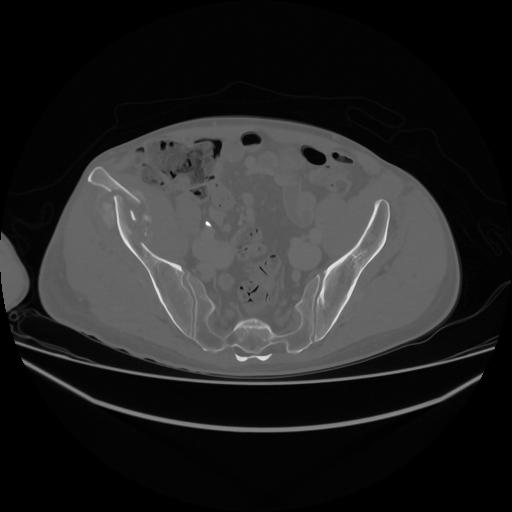

5 CUERPO,CE,Vol,1.0,CUERPO,,